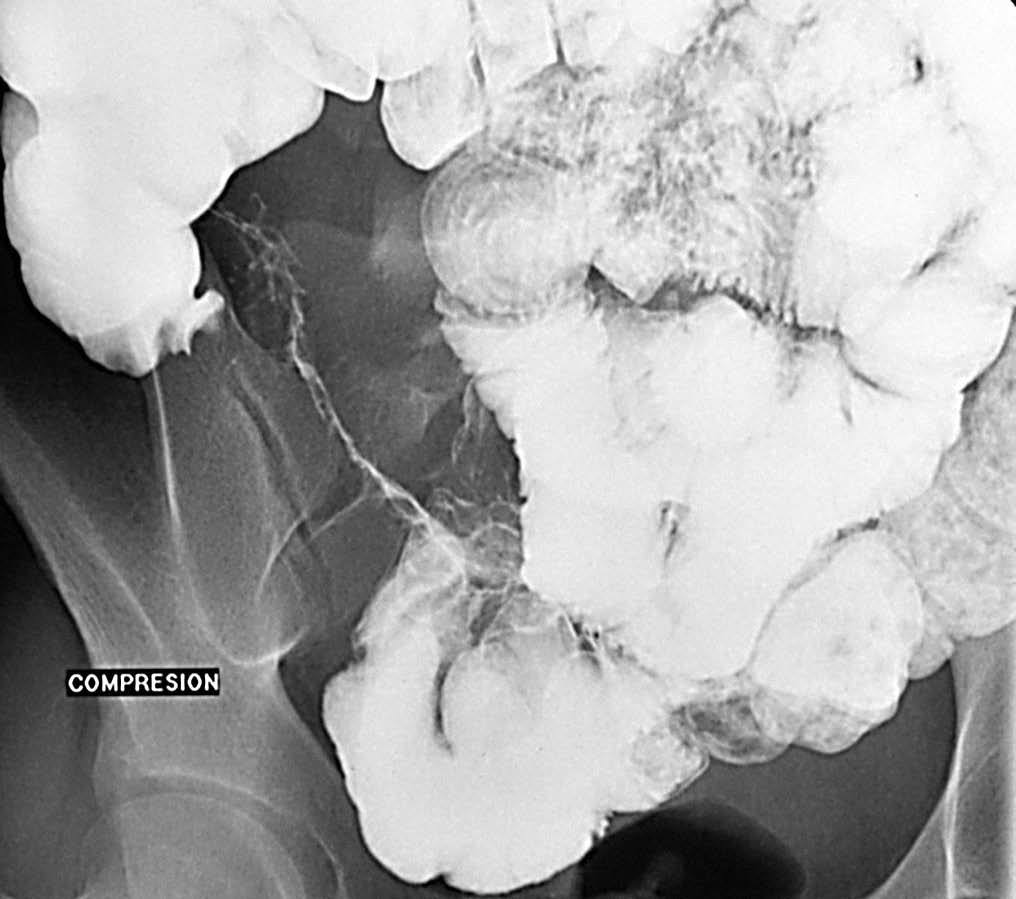

En la etapa inicial los hallazgos propios de la EII en el tránsito baritado son muy sutiles, tal vez discreto grado de espasmo con cierto grado de irritabilidad o alteración de la distensibilidad. De ahí que el estudio baritado tiene que ser realizado con una técnica exquisita, con sumo detalle, con compresión cuidadosa de cada una de las diferentes asas (fig. 3).

Fig. 3.--Enfermedad de Crohn, fase activa inflamatoria. (A) Discreto enderezamiento, rectificación y engrosamiento de pliegues intestinales a nivel de las asas yeyunales. (B) La correlación de tomografía computarizada (TC) muestra la hiperemia y la estratificación tan propias de la situación inflamatoria activa de la pared intestinal.